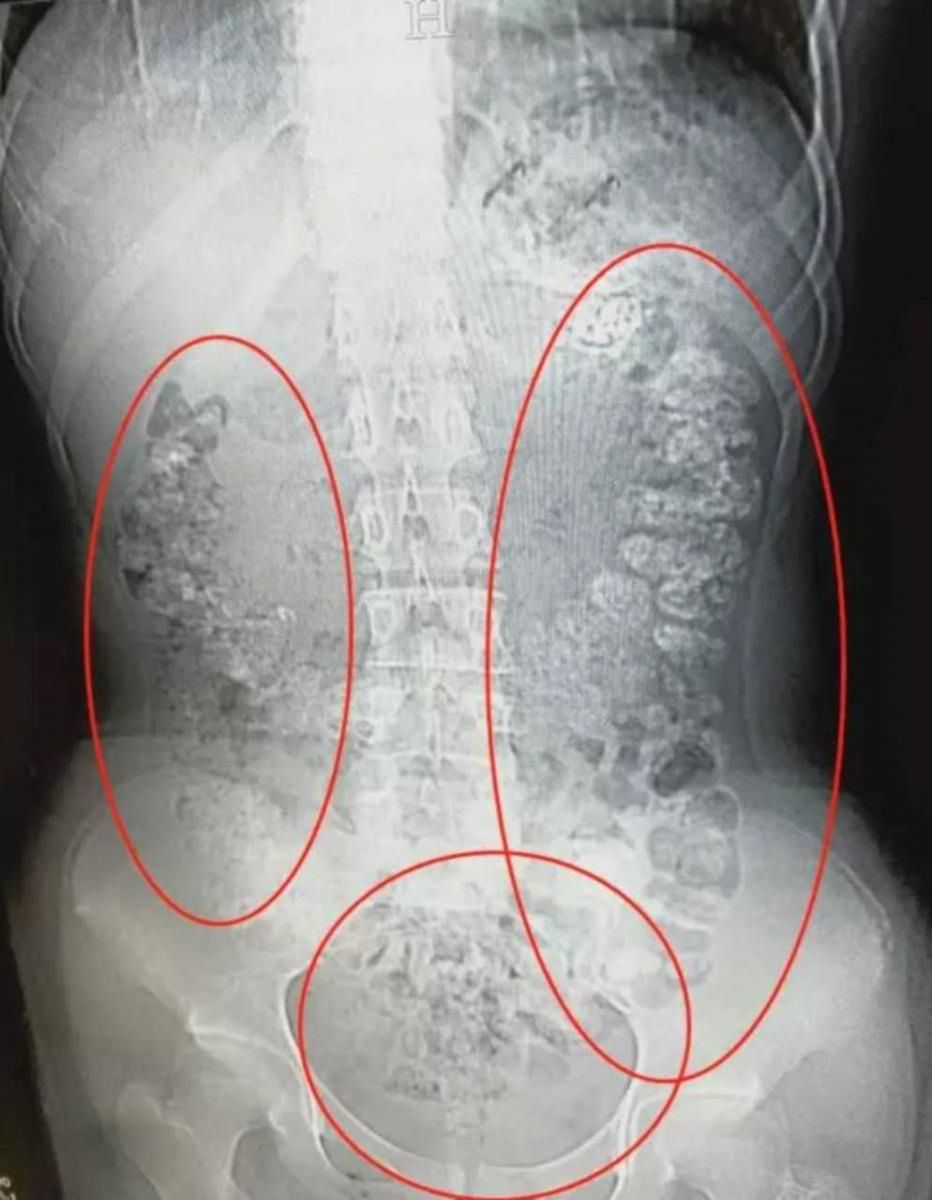

Lekarz uważają, że do rozwoju choroby doprowadziło częste picie bubble tea

Lekarz uważają, że do rozwoju choroby doprowadziło częste picie bubble tea © East News

Tam lekarze zdiagnozowali u niego ciężką postać dny moczanowej. Po szczegółowej analizie okazało się, że nastolatek był uzależniony od bąbelkowej herbaty tzw. bubble tea. Każdego dnia wypijał co najmniej jeden kubek napoju, który jest wysokokaloryczny i zawiera bardzo duże ilości cukru.

Dna moczanowa to choroba zapalna stawów. Jest spowodowana wytrącaniem się w płynie stawowym lub innych tkankach kryształków kwasu moczowego. Dna moczanowa atakuje stawy, w późniejszym okresie uszkadza inne narządy: nerki, serce, naczynia krwionośne, oczy.

Każdy człowiek ma określoną normę kwasu moczowego we krwi. Kiedy jego stężenie przekroczy dopuszczalny poziom, wówczas organizm nie radzi sobie z jego wydalaniem. Kwas moczowy zaczyna się krystalizować i osiada na stawach, raniąc przy tym tkankę.